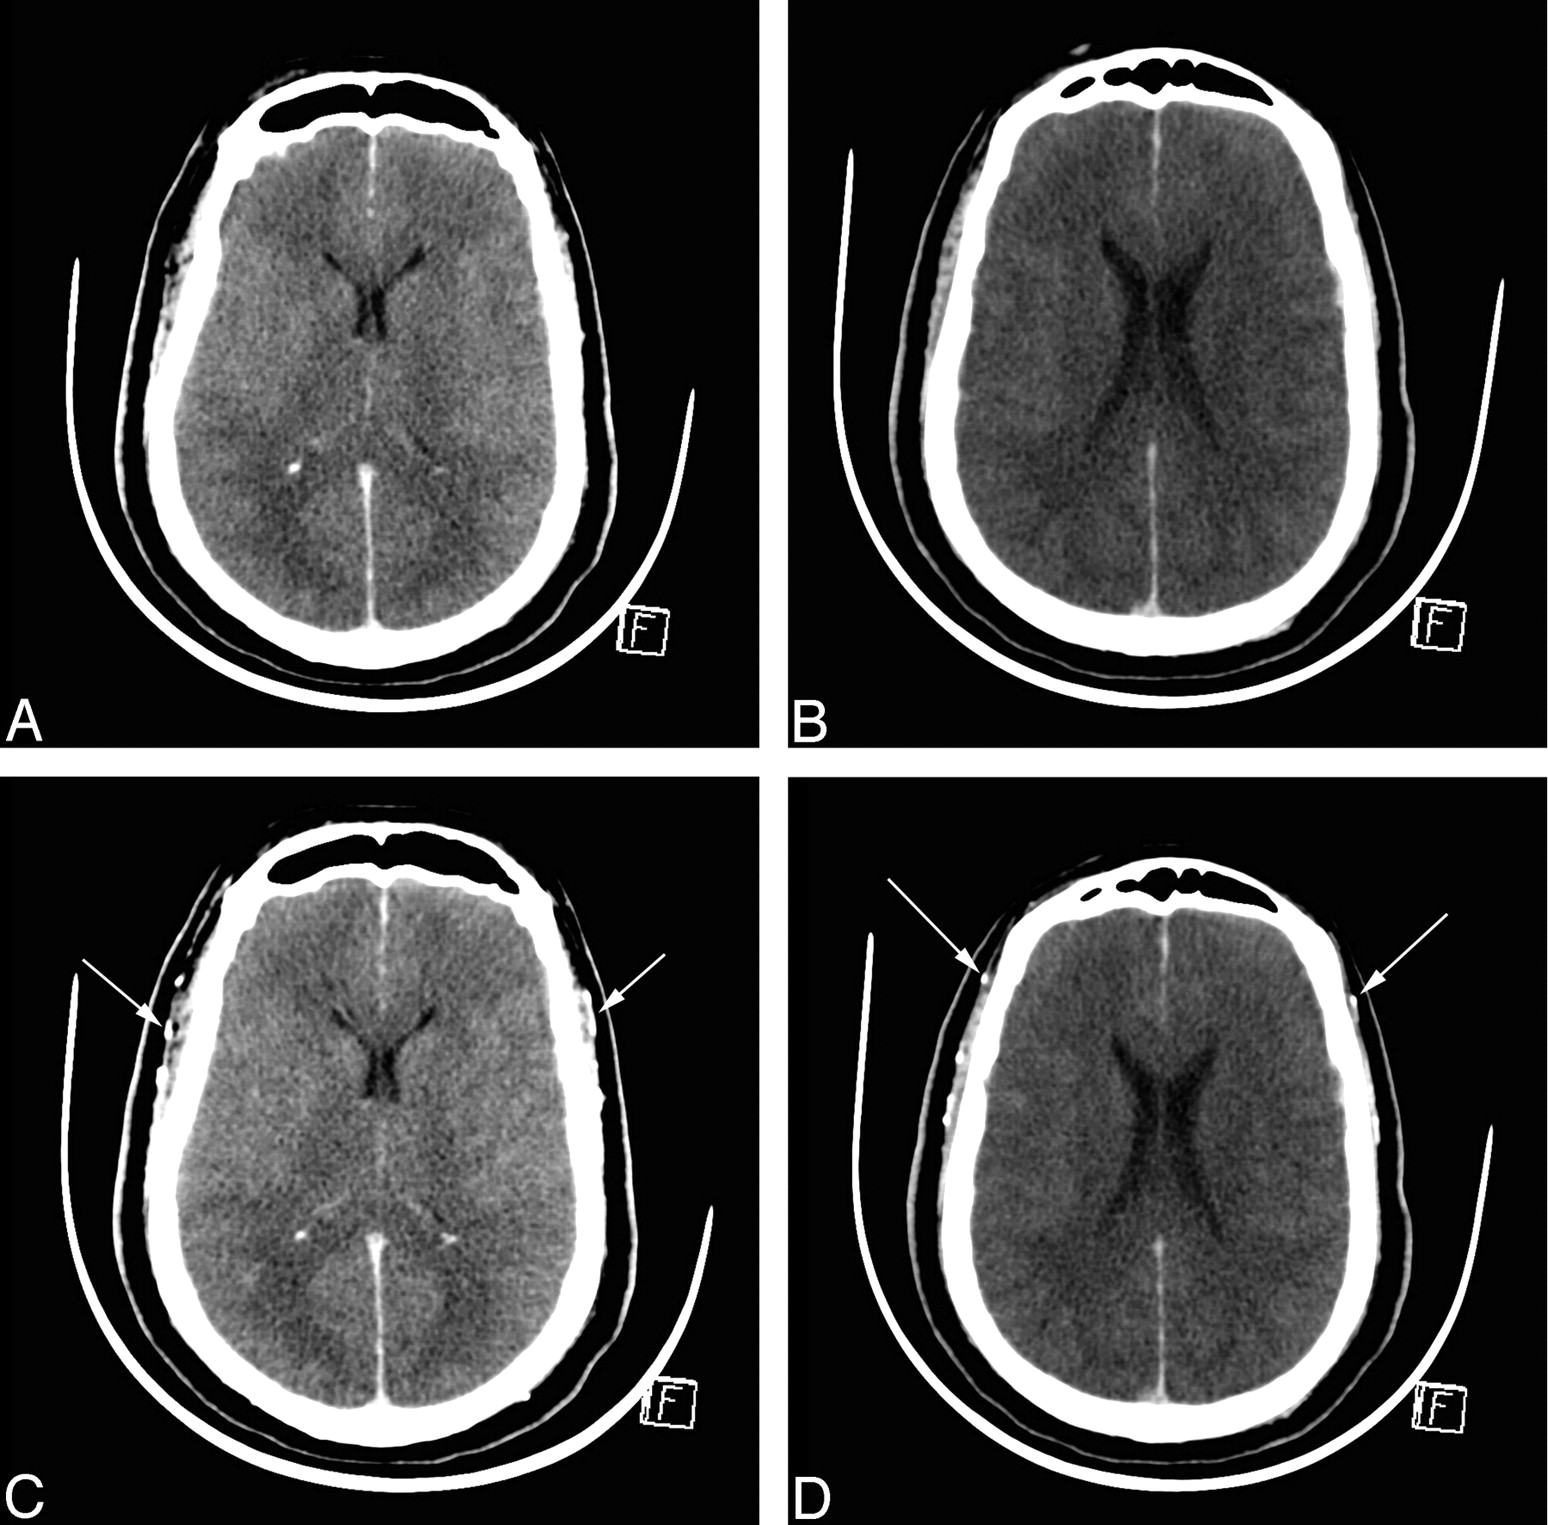

CTA in BD before and 60 seconds after contrast medium injection. A and B, Unenhanced CT sections. C and D, Corresponding CT sections with identical window settings 60 seconds after contrast medium injection, demonstrating cerebral CT silence: absence of visualization of ICVs and cortical segments of the MCAs. Both superficial temporal arteries are opacified, indicating that contrast medium has been correctly injected (arrows).